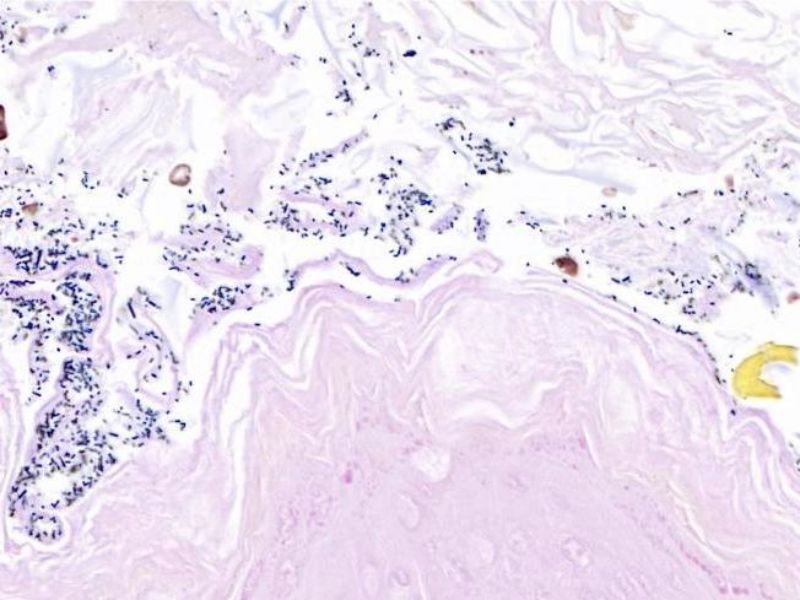

※实验结果示例:

革兰氏阳性细菌------蓝紫色

革兰氏阴性细菌-----粉红色

细胞核------红色

革兰氏染色